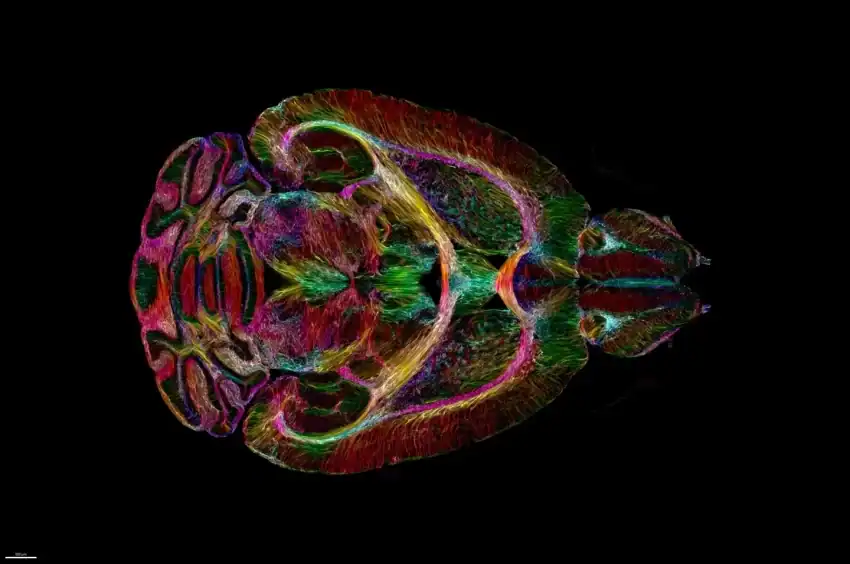

طوّر باحثون من جامعة ديوك تقنية جديدة لتصوير الدماغ تنتج صورًا أكثر وضوحًا بمقدار 64 مليون مرة من فحوصات التصوير بالرنين المغناطيسي القياسية.

كانت هذه التقنية الجديدة المسماة HiDiver، قادرة على إنتاج صور للخلايا العصبية الفردية واتصالاتها في دماغ الفأر.

كما تجمع تقنية HiDiver بين طريقتين مختلفتين للتصوير: التصوير بالرنين المغناطيسي والفحص المجهري للصفائح الخفيفة.

وتستخدم تقنية HiDiver التصوير بالرنين المغناطيسي لإنشاء صورة خشنة للدماغ، ثم تستخدم المجهر الضوئي لإنشاء صورة عالية الدقة لمنطقة معينة من الدماغ، ثم يتم دمج الصورتين لإنشاء صورة عالية الدقة للدماغ بأكمله.